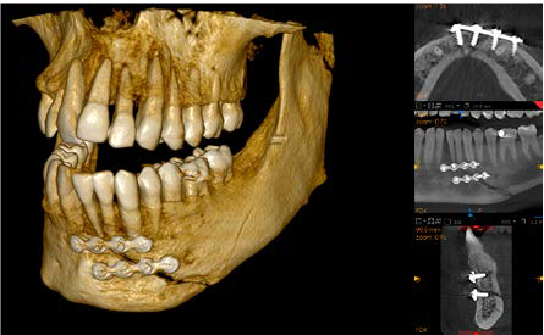

Cirugía bucal y maxilofacial

El CS 9600, que ofrece hasta 14 campos de visión, incluida radiología de cráneo completo y ATM, es idóneo para cirugía maxilofacial y ortognática.